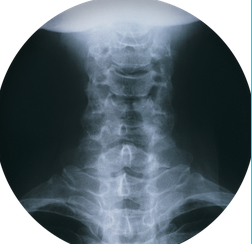

목디스크는 경추나 흉추 디스크가 손상되어 디스크와 인접한 신경이 압박되거나 자극되어 발생하는 증상입니다. 목디스크는 목의 디스크나 척추의 디스크에 문제가 생기면 발생할 수 있으며, 디스크가 실명하거나 이동할 경우 디스크와 인접한 신경에 압력이 가해져 통증이나 저림 현상, 근육 약화 등의 증상이 나타날 수 있습니다. 일상생활에서 나쁜 자세, 긴 시간 동안의 앉아서의 생활습관, 충격적인 스포츠 활동 등이 원인이 될 수 있으며, 적절한 치료 없이는 만성화되어 치명적인 신경증상으로 이어질 수 있으므로 조기 진단과 적절한 치료가 필요합니다.

목 디스크 원인

목 디스크의 주요 원인은 디스크의 손상이나 변형으로 인한 것입니다. 목 디스크는 경추나 흉추 디스크에 문제가 생길 때 발생할 수 있으며, 다음과 같은 원인으로 인해 디스크에 손상이 생길 수 있습니다: